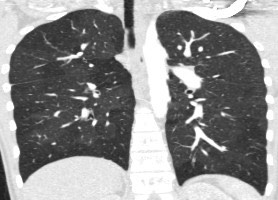

2966. У пациента 15 лет при выполнении компьютерной томографии в обоих легких определяются участки понижения пневматизации, формирующие картину «лоскутного одеяла», единичные кальцинаты, визуализируются единичные бронхоэктазы субсегментарных бронхов, рентгенологическая картина соответствует